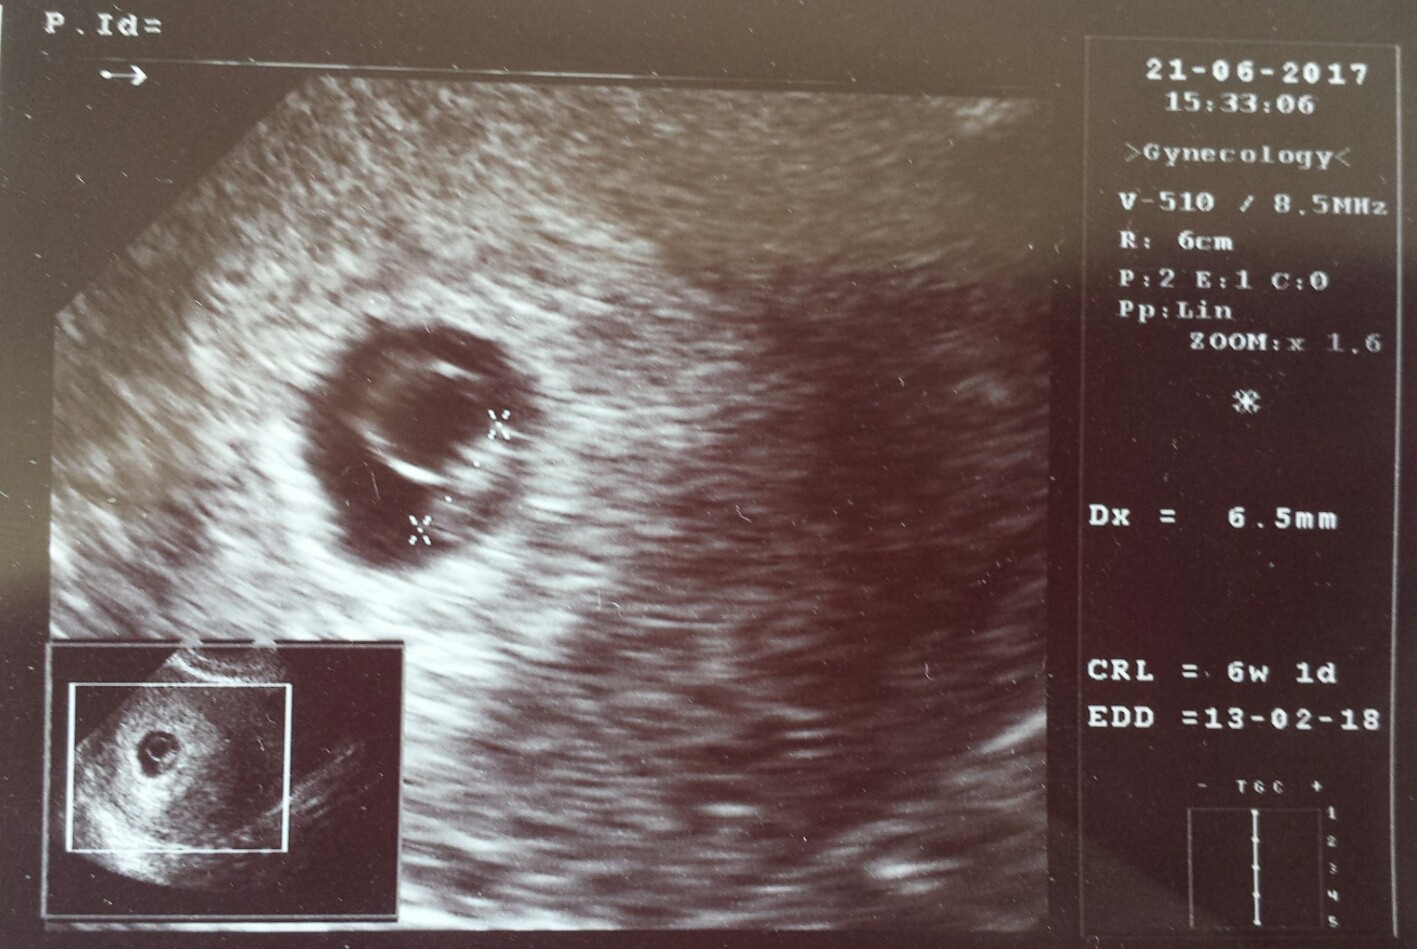

Zdjęcia - testy, usg, brzuszki :)

Zapraszam do pochwalenia się zdjęciami dwóch kreseczek, brzuszków i maluszków :)

1497509411-aaaaaa.jpeg